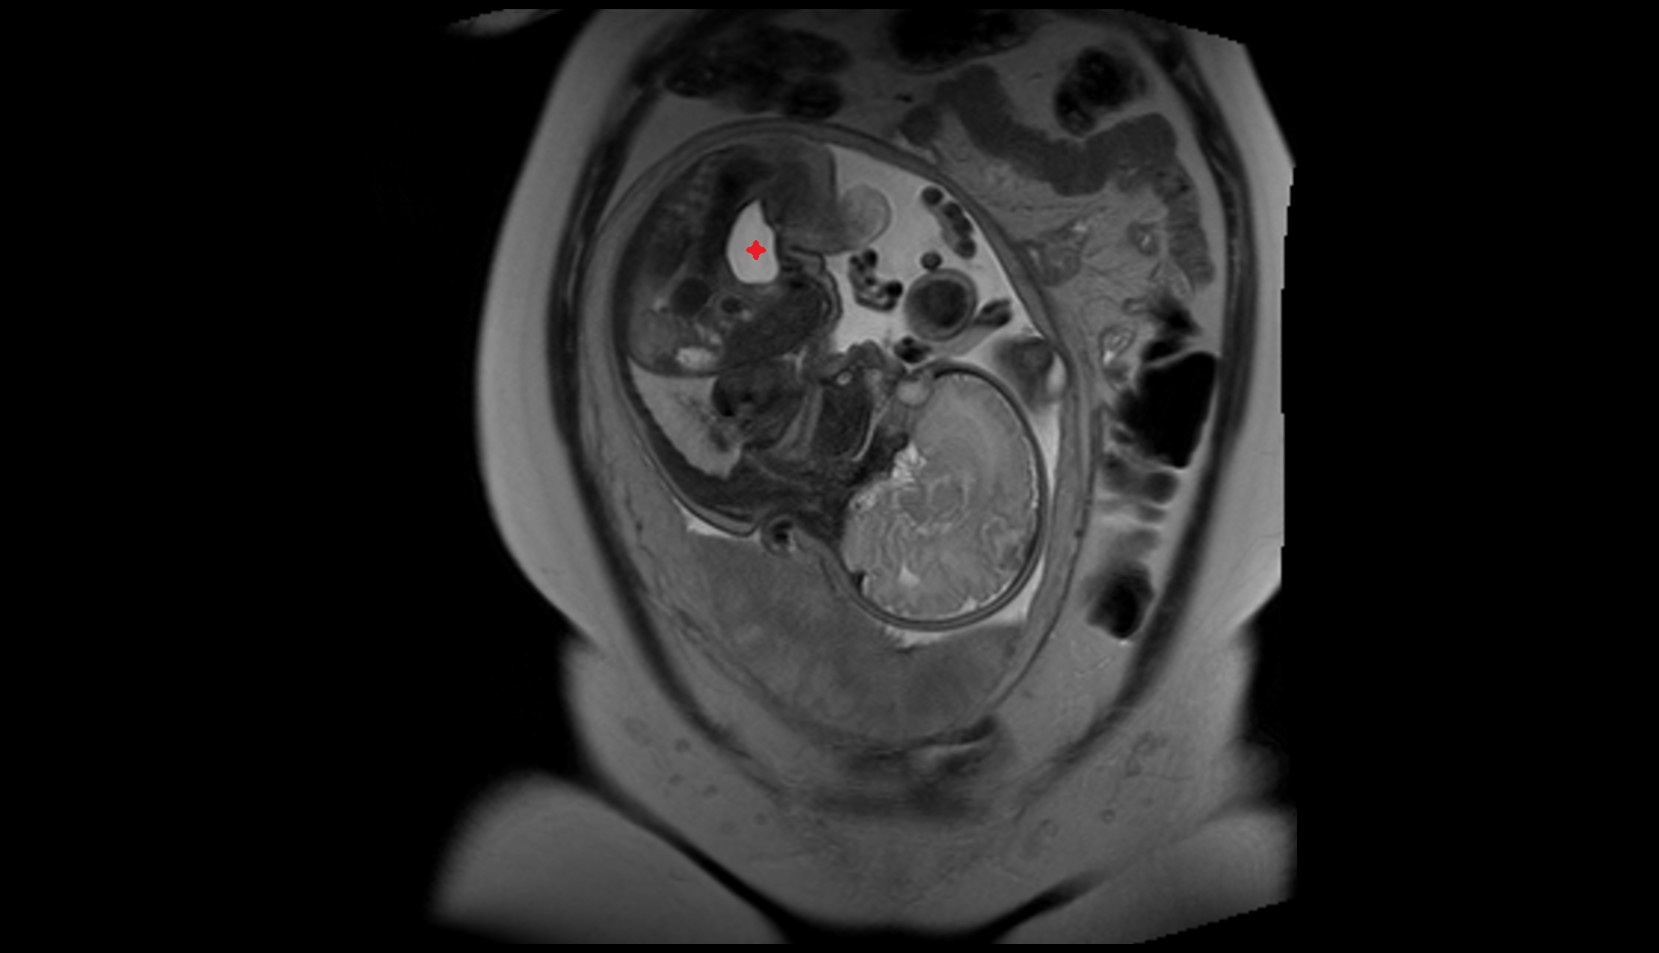

- Placenta

- Uterus (pregnancy)

- Amniotic fluid

- Umbilical cord

- Urinary Bladder in Pregnancy

- Cervix in Pregnancy

- Vagina in Pregnancy

- Fundus of uterus in pregnancy

- Fetal brain

- Maternal ovaries